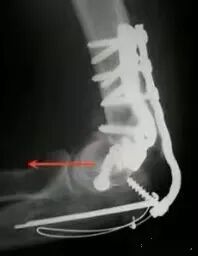

最难的最难的。。。灾难级的!当开放骨折+大量骨缺损遇到了感染你会怎么办?

30岁年轻男性

病例的结局

一期行外固定架+抗生素骨水泥控制感染,这个是常规的。

下一步?

二期同种异体肘关节移植术!并且将三头肌支点与原肘进行了重建

术后18个月,出现了失败和关节的不稳,但宿主和自体骨较好的结合了。

又进行了第二次肘移植,最后终于愈合